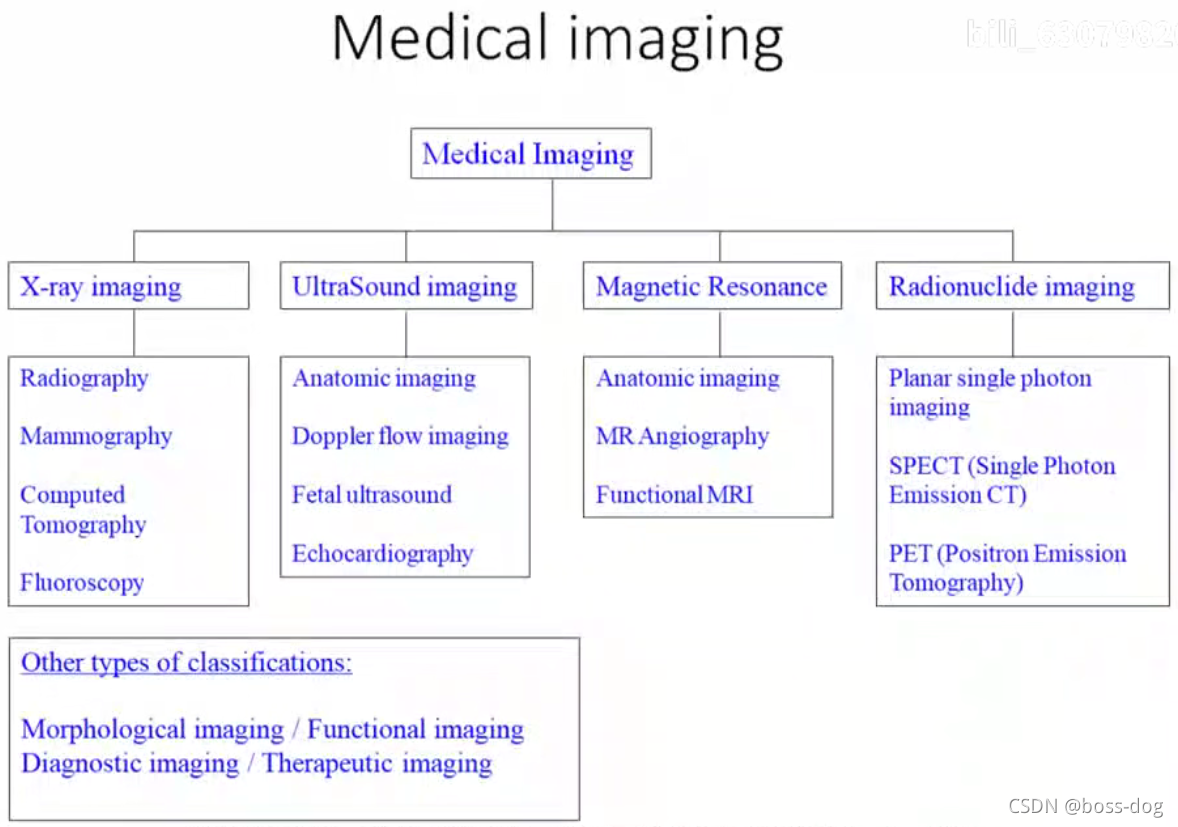

医学成像技术分类:

1.X光成像(X-ray imaging)。有核辐射,需要采用高能量的X光或者伽马光子;应用领域如胸透、拍片、乳腺癌钼靶成像、CT(Computed Tomography,通过旋转拍摄得到不同角度透射的图片,然后根据这个图片来做重建,最后得到人体横断面的图片)、荧光成像(Fluoroscopy)。

2.超声成像(UltraSound imaging)。没有那些辐射而且用的是声波,只不过频率要比声波要高,所以是安全的且特别方便,应用领域如解剖成像(Anatomical imaging)、多普勒超声(Doppler flow imaging,可以测量血管里面血流的速度和方向)、胎儿成像(Fetal Ultrasound)、心脏的超声成像(Echocardiography)。

3.磁共振成像(Magnetic Resonance,MR)。采用的是射频电波,安全且没有核辐射;应用领域如解剖成像(Anatomical imaging)、磁共振做血管成像(MR Angiography)、磁共振做功能成像(Functional MRI)。

4.核素成像(Radionuclide imaging)。有核辐射,需要采用高能量的X光或者伽马光子;应用领域如单光子平面或成像(Planar single photon imaging)、单光子发射的CT(Single Photon EmissionCT,SPECT)、正电子发射成像(Positron Emission Tonography),这三类都是需要通过往人体里面进行静脉注射一种核素,这种核素需要释放出光子或者释放出正电子来回到它的稳态,如果释放出光子,这光子高能光子穿过人体就会被探测器接收到,然后用来做成像。

其他的分类,譬如形态学成像(Morphological imaging,一种就是只反映出来各个器官的形态大小形状),功能成像(Functional imaging,就是反映出来每个器官的功能血流或者供血从而成像),诊断成像(Diagnostic imaging),治疗成像(Therapeutic imaging)。